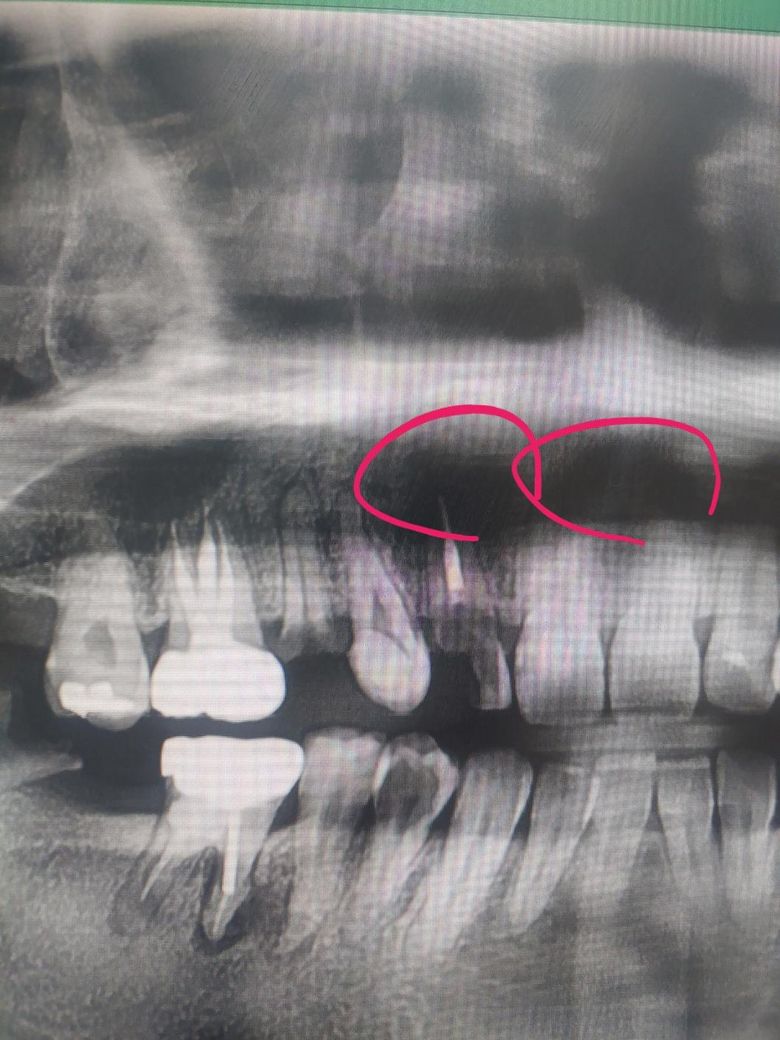

치아 파노라마 상에 앞니들 위에 부분이 검게 보이는데 뿌리랑 잇몸뼈가 녹은걸까요?

치아 파노라마 상에 앞니들 위에 부분이 검게 보이는데요 혹시 치아 뿌리랑 잇몸 뼈가 녹은걸까요...............?

파노라마 방사선 사진은 왜곡, 중첩 등이 많이 발생합니다. 위 파노라마 사진상에서 검은 부분은 입천장과 혀 등이 겹쳐서 그렇게 보이는 것이고 실제로 뼈가 녹거나 그렇지는 않았을 것입니다.

파노라마 상에서 검게 나타나는 부분이 모두 염증을 의미하지 않으며 해당부분은 염증은 아닙니다.

사진상의 오류일수도 잇고 연조직과 겹쳐보이면서 그렇게 보일수도 잇고 콧구멍이나 상악동같은 곳입니다.

치아 파노라마 상에 앞니들 위에 부분이 검게 보이는 경우 혹시 치아 뿌리랑 잇몸 뼈가 흡수되어 그림자져서 보입니다. 염증이 있을 가능성이 높으며, 치아 뿌리 주변에 염증이 생기면, 그 부위의 뼈가 흡수되어 검은 그림자로 나타날 수 있습니다.

보다 정확한 상태 확인을 위해서는 우선 치과에 방문하여 실제로 상태를 확인해보길 권합니다.

방사선 사진으로 해당 부위는 검게 보일 수 있습니다. 충치가 있어. 부러진 채 뿌리는 치근단 질환이 있을 가능성이 높아 보이나 방사선 사진으로는 정확한 확인이 어려워보입니다. 이런 경우에는 치근단 사진이나 CT 촬영을 통해서 확인을 할 수 있습니다.